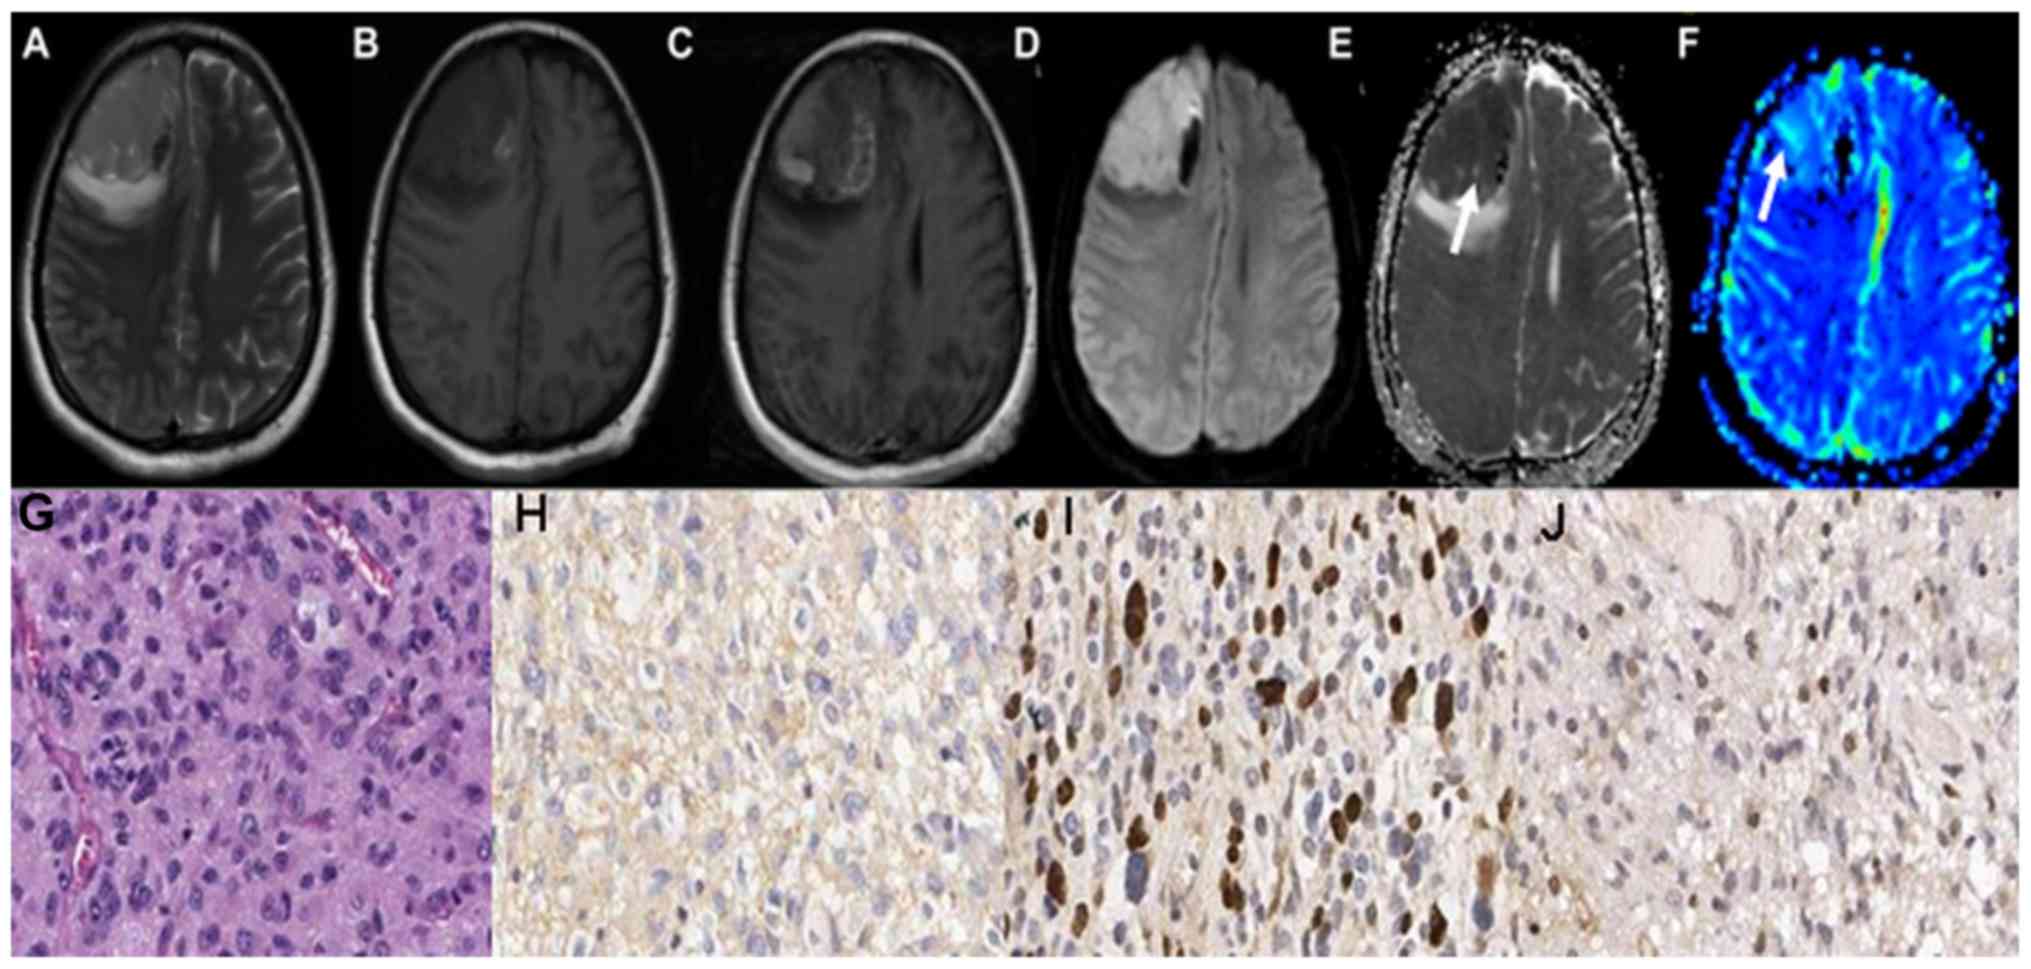

The maps of the aforementioned conventional MRI scans of grade II astrocytoma are demonstrated in Fig. 1A-C. Grade II astrocytoma exhibited low signal on DWI sequence, and high ADC values, as illustrated in Fig. 1D and E. The parenchyma of grades II astrocytoma on the rCBV maps exhibited low signals, as illustrated in Fig. 1F-J demonstrate the HE staining map, IHC. GFAP map, IHC. Topo IIα map and IHC. MGMT map of grades II astrocytoma respectively. The conventional MRI scans of grade III astrocytoma are demonstrated in Fig. 2A-C. Grade III astrocytoma demonstrated high signal on DWI sequence, and the ADC values of the tumor parenchyma were lower, as illustrated in Fig. 2D and E. The parenchyma of grades III astrocytoma on the rCBV maps exhibited high signals, as illustrated in Fig. 2F-J demonstrate the HE staining map, IHC. GFAP map, IHC. Topo IIα map and IHC. MGMT map of grades III astrocytoma respectively. The conventional MRI scans of grade IV astrocytoma are demonstrated in Fig. 3A-C. Grade IV astrocytoma demonstrated the highest signal on the DWI maps, and the ADC values were the lowest between all of the astrocytoma grades, as illustrated in Fig. 3D and E. The grade IV astrocytoma on the rCBV map demonstrated the highest signal, as illustrated in Fig. 3F-J demonstrate the HE staining map, IHC. GFAP map, IHC. Topo IIα map and IHC. MGMT map of grades IV astrocytoma respectively.

Figure 3.

Right occipital lobe glioblastoma multiforme (Grade IV) in a 59-year-old male. (A) The cystic wall of the right occipital lobe lesion demonstrated a iso-intense signal on T1 and (B) T2WI, and the cystic fluid was hypo-intense on T1WI and hyper-intense on T2WI. (C) Axial contrast-enhanced T1W image exhibited marked enhancement of the cystic wall. (D) The cystic wall demonstrated a hyper-intense signal on diffusion-weighted imaging map. (E) The apparent diffusion coefficient value was low in the cystic wall (arrow). (F) The relative cerebral blood volume value was highest in the cystic wall (arrow). (G) Poorly differentiated tumor cells with remarkable nuclear atypia with nucleolar enlargement and increased karyokinesis were displayed on a hematoxylin and eosin staining map. (H) Low glial fibrillary acidic protein expression level in the cytoplasm. (I) High expression level of topoisomerase IIα in the nucleus. (J) The O 6-methylguanine-DNA methyltransferase proteins displayed low expression levels in the nucleus. WI, weighted image.